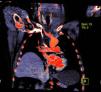

La TC muestra un gran hematoma latero-cervical izquierdo y una extravasación de contraste procedente de la pared anterior del tronco braqueocefálico a 3 cm de su salida desde la aorta (fig. 2).